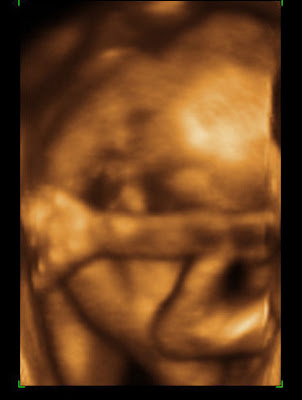

Here are a few pictures of the little one. Turns out it’s a very flexible little baby. Nope, that’s not it’s elbow by its face, it’s the knee!!!! It’s body is in a V shape, with its legs fully extended. Then it curled up into a tiny little ball, but not by crossing its legs into its belly, but by bending its knees down and rolling back up.

I had a feeling it was curled in a little ball because it felt different compared to the other kids. Also, I find it very painful at times and during the u/s saw why. I kept thinking it was kicking and punching my round ligaments. But nope, I sat and watched the moment that it turned its head, arched as far back as it could and stretch!!! THAT is painful–so all this time it’s actually the stretching that has been so painful and those aren’t kicks and punches I’m feeling on those round ligaments, it’s a tiny bottom pushing back against them.

As for the gender, when it wasn’t stretched out, it was in such a tight ball that the u/s tech said there’s just no way we’re going to know the gender until he or she comes out. So, that’s it. One would think the baby would be more comfortable flipping around, but nope, it likes curling up and moving around as a yoga/pilates expert. As much as the u/s tech said she couldn’t see anything, I swear I saw boy parts, but Andrew says my mind is playing tricks on me.